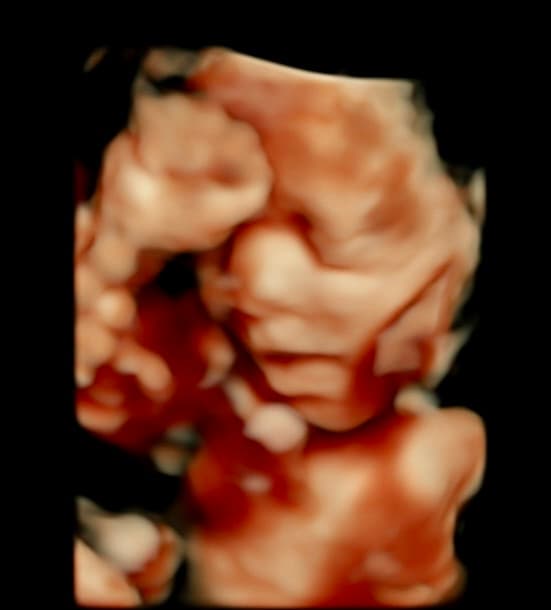

Book NowTahlequah's first 3D/4D ultrasound studio

At Magnolia Fetal Imaging, we provide a warm, relaxing environment where you can bond with your baby through advanced 3D/4D & HD ultrasound technology. Our studio focuses on capturing precious keepsake moments for families — gender reveals, early looks, and high‑definition images you will cherish for a lifetime.

All sessions are non‑diagnostic and designed purely for bonding and keepsake entertainment.